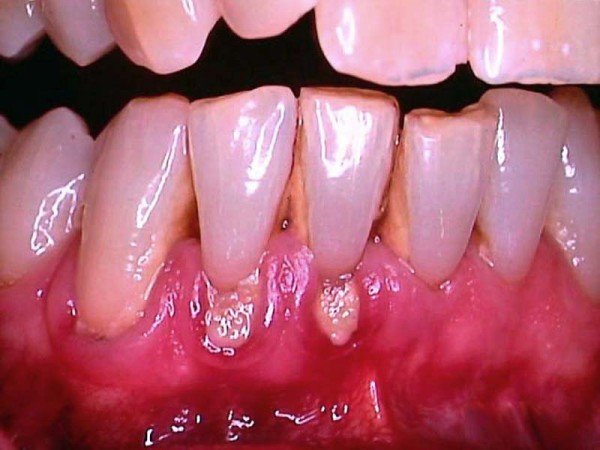

Фото

Рак десны — серьезное заболевание, вызывающее множество вопросов и беспокойств. На ранних стадиях его симптомы могут быть едва заметны, что задерживает диагностику. Рак может проявляться мелкими язвочками или покраснениями, которые часто игнорируются. Однако именно в этот период лечение наиболее эффективно, и вероятность полного выздоровления возрастает.

С развитием болезни появляются более выраженные симптомы: боль, кровоточивость десен и трудности при жевании. Важно не откладывать визит к стоматологу при первых подозрениях. Регулярные осмотры и забота о здоровье могут спасти жизнь. Ранняя диагностика и своевременное лечение — ключевые аспекты в борьбе с этим заболеванием. Будьте внимательны к своему организму и не стесняйтесь обращаться за медицинской помощью.

- Изменение оттенка мягких тканей и их уплотнение. При этом десна выглядит покрасневшей, а на ней местами появляются белые мутные пятна или точки. Иногда их них выделяется гной.

- Любые новообразования на слизистой, особенно если они выглядят белыми, мутными или имеют вид язвочек.